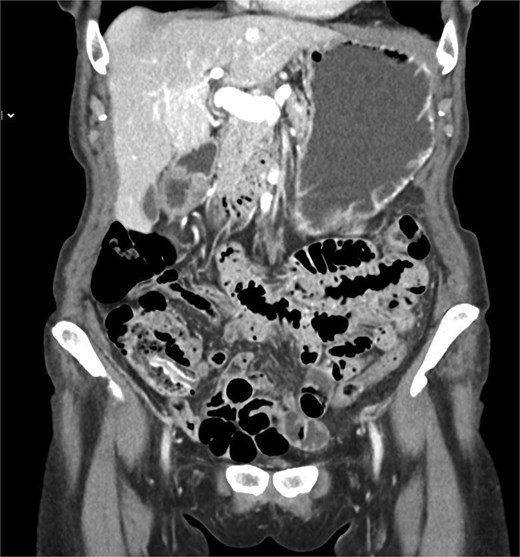

The outpatient abdominal CT images were reviewed, and the diagnosis of an inverted appendix was confirmed (Fig. 2).

Coronal contrast-enhanced CT scan demonstrating an elongated structure projecting into the cecal lumen from the appendiceal orifice, consistent with an inverted appendix.